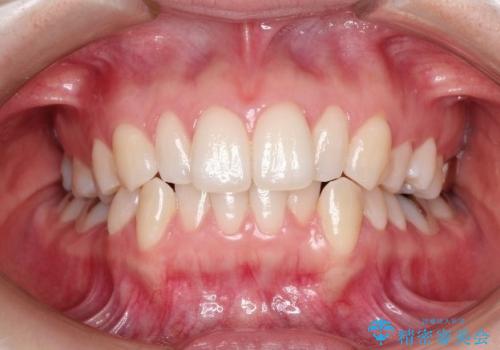

- 前歯の正中離開の改善を希望され来院された患者様です。

見た目、噛み合わせ及び、治療期間や施術内容に大変ご満足いただきました。